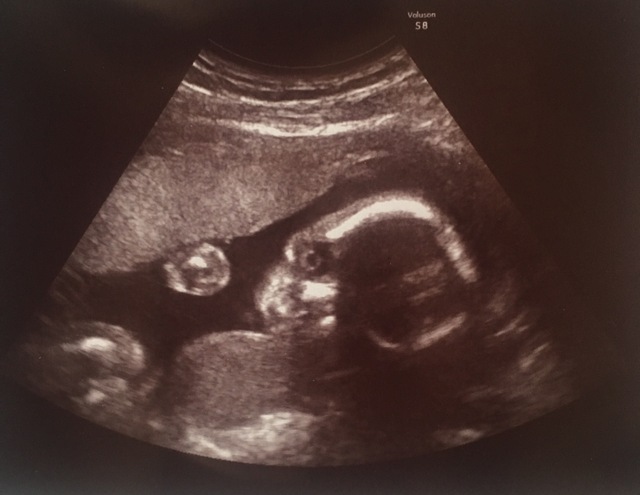

22週3日(22w3d・女の子)|なっちゃんジュース さん(27歳)

エコー写真撮影時のエピソード:

妊娠初期途中から逆子になり、このエコーの時も逆子でした。エコーの時はだいたい顔を隠していて、毎回見えない状態。初期は悪阻が酷かったのですが、この時は徐々に落ち着いてた時でした。

このエコーではV字バランスの様な姿勢を取っており、エコーを見て足が長いとか、運動神経良さそう、と、旦那や両親と話していました。